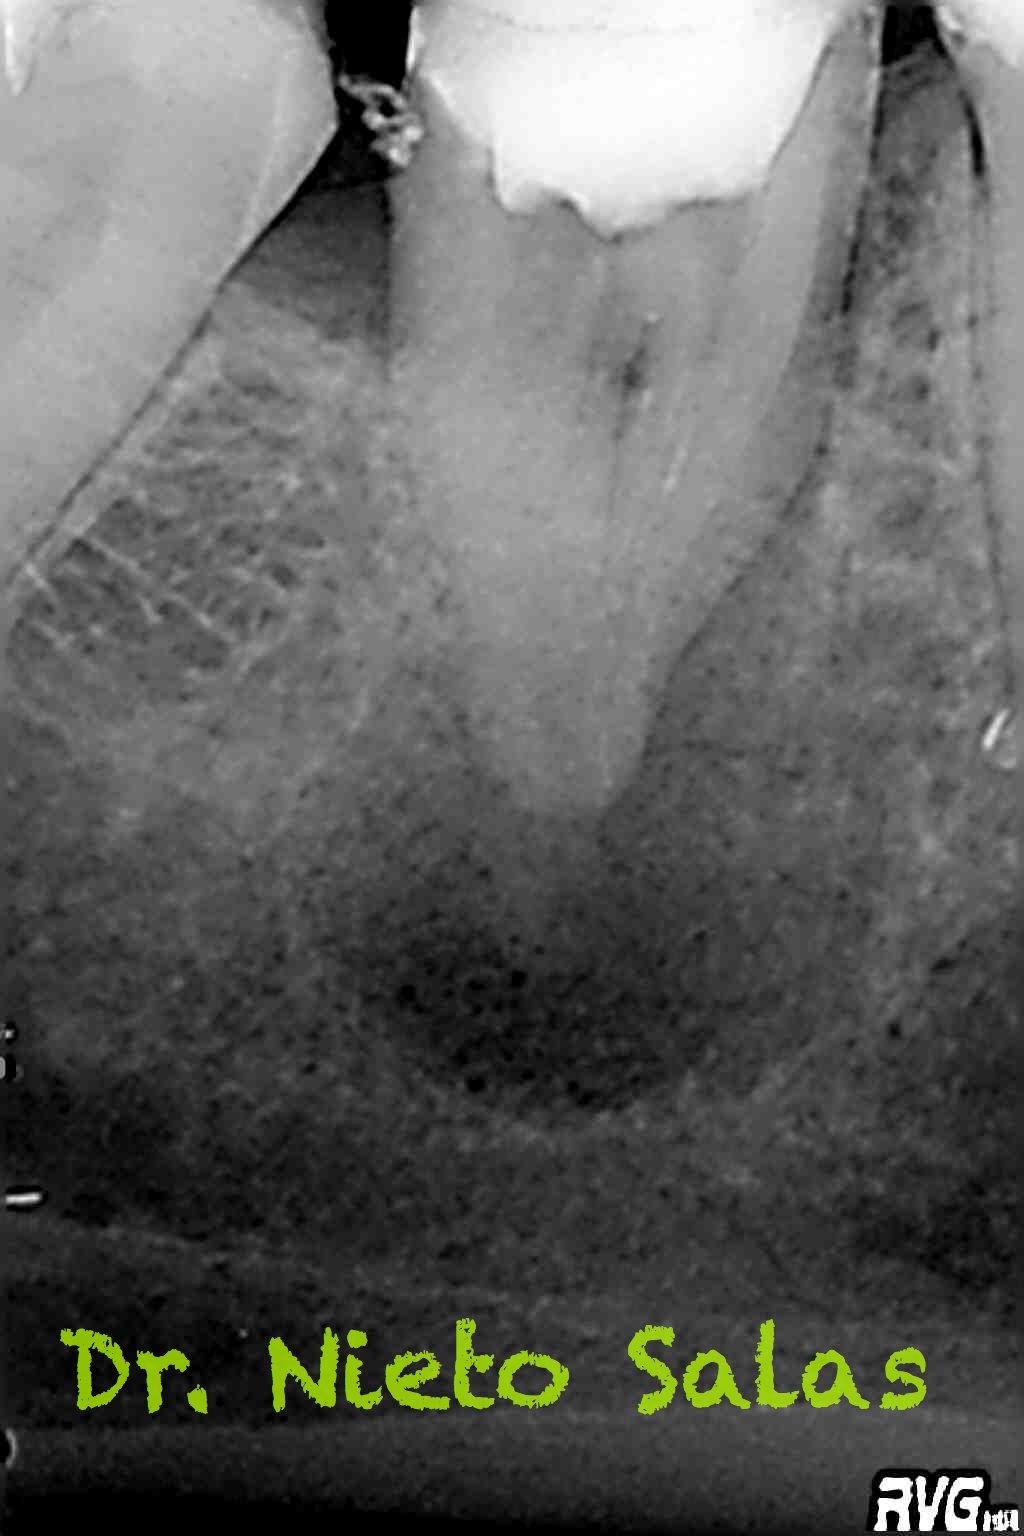

Una vez que tenemos todo preparado, se trata de un tratamiento de endodoncia convencional, con lo que seguiremos los pasos de limpieza, conformación y sellado del sistema de conductos.

Usamos técnica de obturación por ola continua de Buchanan modificada y hacemos un backfilling con gutapercha inyectada.

Me gusta ser conservador con los diámetros apicales, para deformarlos lo menos posible. En este caso no fue así por la anatomía que presentaba, adapté bien los conos maestros con un diámetro más o menos 45 en el conducto distal(recuerda que era acintado con lo que no es posible un único cono apical) y 30 los mesiales.